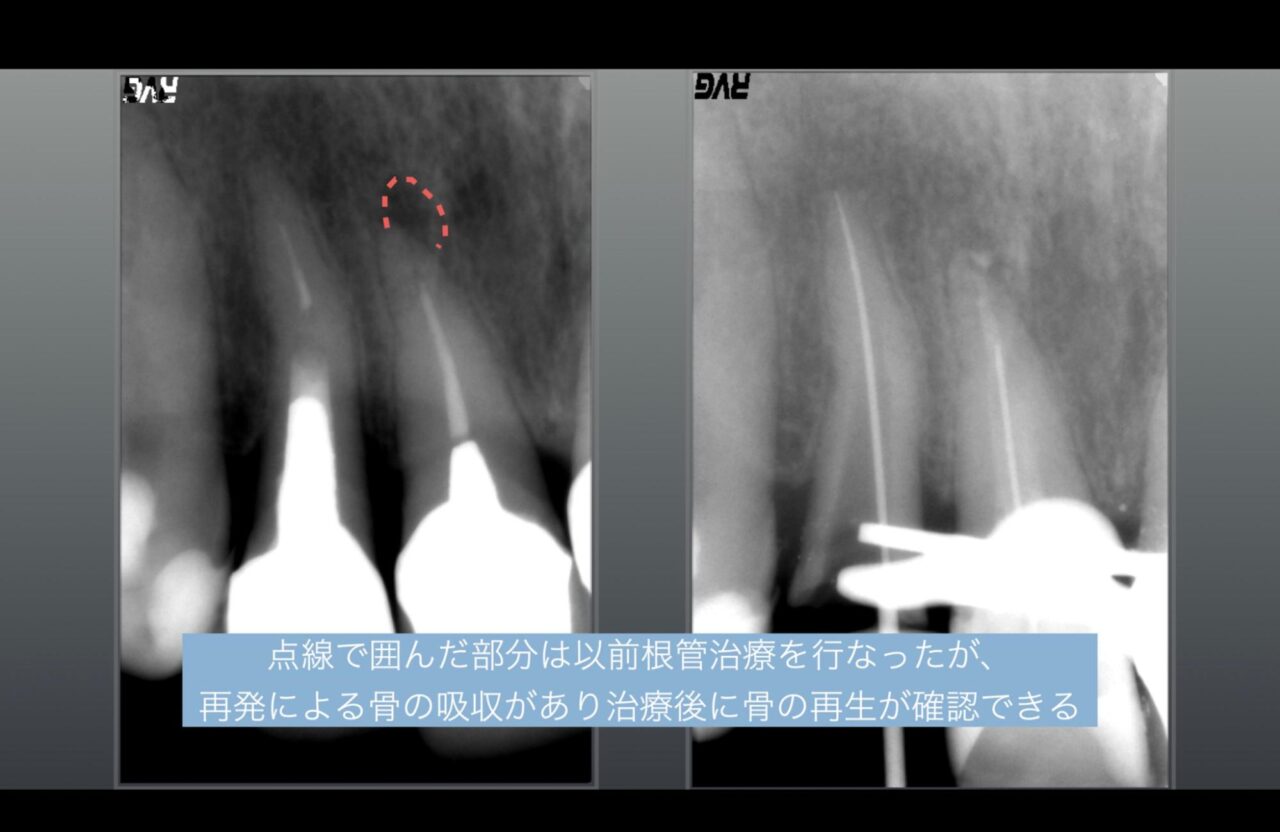

症例1:根管治療後に骨の吸収があり、治療後に骨の再生

このレントゲンの比較写真は、左のレントゲンだと点線で囲んだ部分の骨吸収が認められますが、治療後、数ヶ月で骨の再生が起こり、神経がある歯と同じようなレントゲン像の様になります。